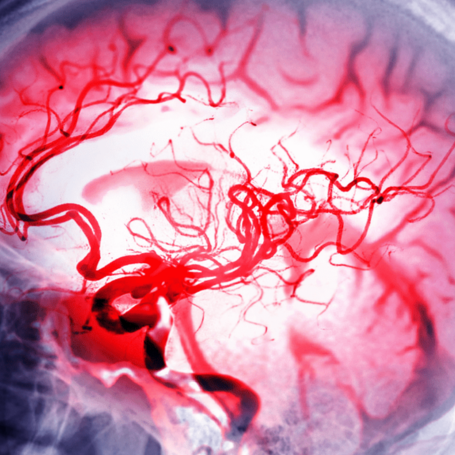

Hemorragias Cerebrales

Tipos: Las hemorragias cerebrales incluyen hemorragia parenquimatosa, subaracnoidea, subdural y epidural. Se diferencian por su localización y gravedad, y pueden ser espontáneas o traumáticas.

Causas: La más frecuente es la hipertensión arterial. Otras causas incluyen aneurismas, malformaciones arteriovenosas, traumatismos, trastornos de coagulación, uso de anticoagulantes y tumores cerebrales.

Diagnóstico: Se realiza mediante tomografía computarizada (TAC), que es el estudio inicial de elección para detectar sangrado. La resonancia magnética (RM) y la angiografía ayudan a identificar la causa y extensión del sangrado. También se evalúa el estado neurológico del paciente.